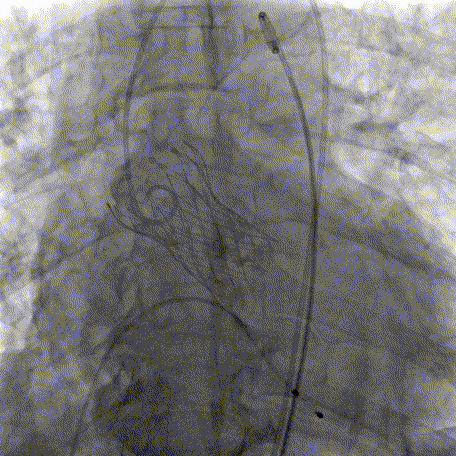

术前主动脉根部造影

20mm球囊预扩

AV26瓣膜定位

AV26瓣膜工作位造影

AV26瓣膜释放

术后主动脉根部造影

本例手术为重度钙化二叶式病变重度主动脉瓣狭窄TAVR手术,团块状钙化挤压存在移位瓣周漏风险,术前手术团队对患者进行了全面细致的评估,确定假体瓣膜锚定区域范围,制定术前释放策略。何柳平主任团队通力配合、精准释放,充分利用TaurusElite可回收功能,在瓣膜释放至2/3时,多角度评估瓣膜植入深度、锚定力以及冠脉灌注情况,确认瓣膜植入深度合适、锚定力稳定,缓慢逐个脱钩,进行瓣膜释放。释放后造影显示瓣膜膨胀良好,行血流动力学评估,跨瓣压差从术前100mmHg降至15mmHg,少量瓣周漏,手术圆满完成。